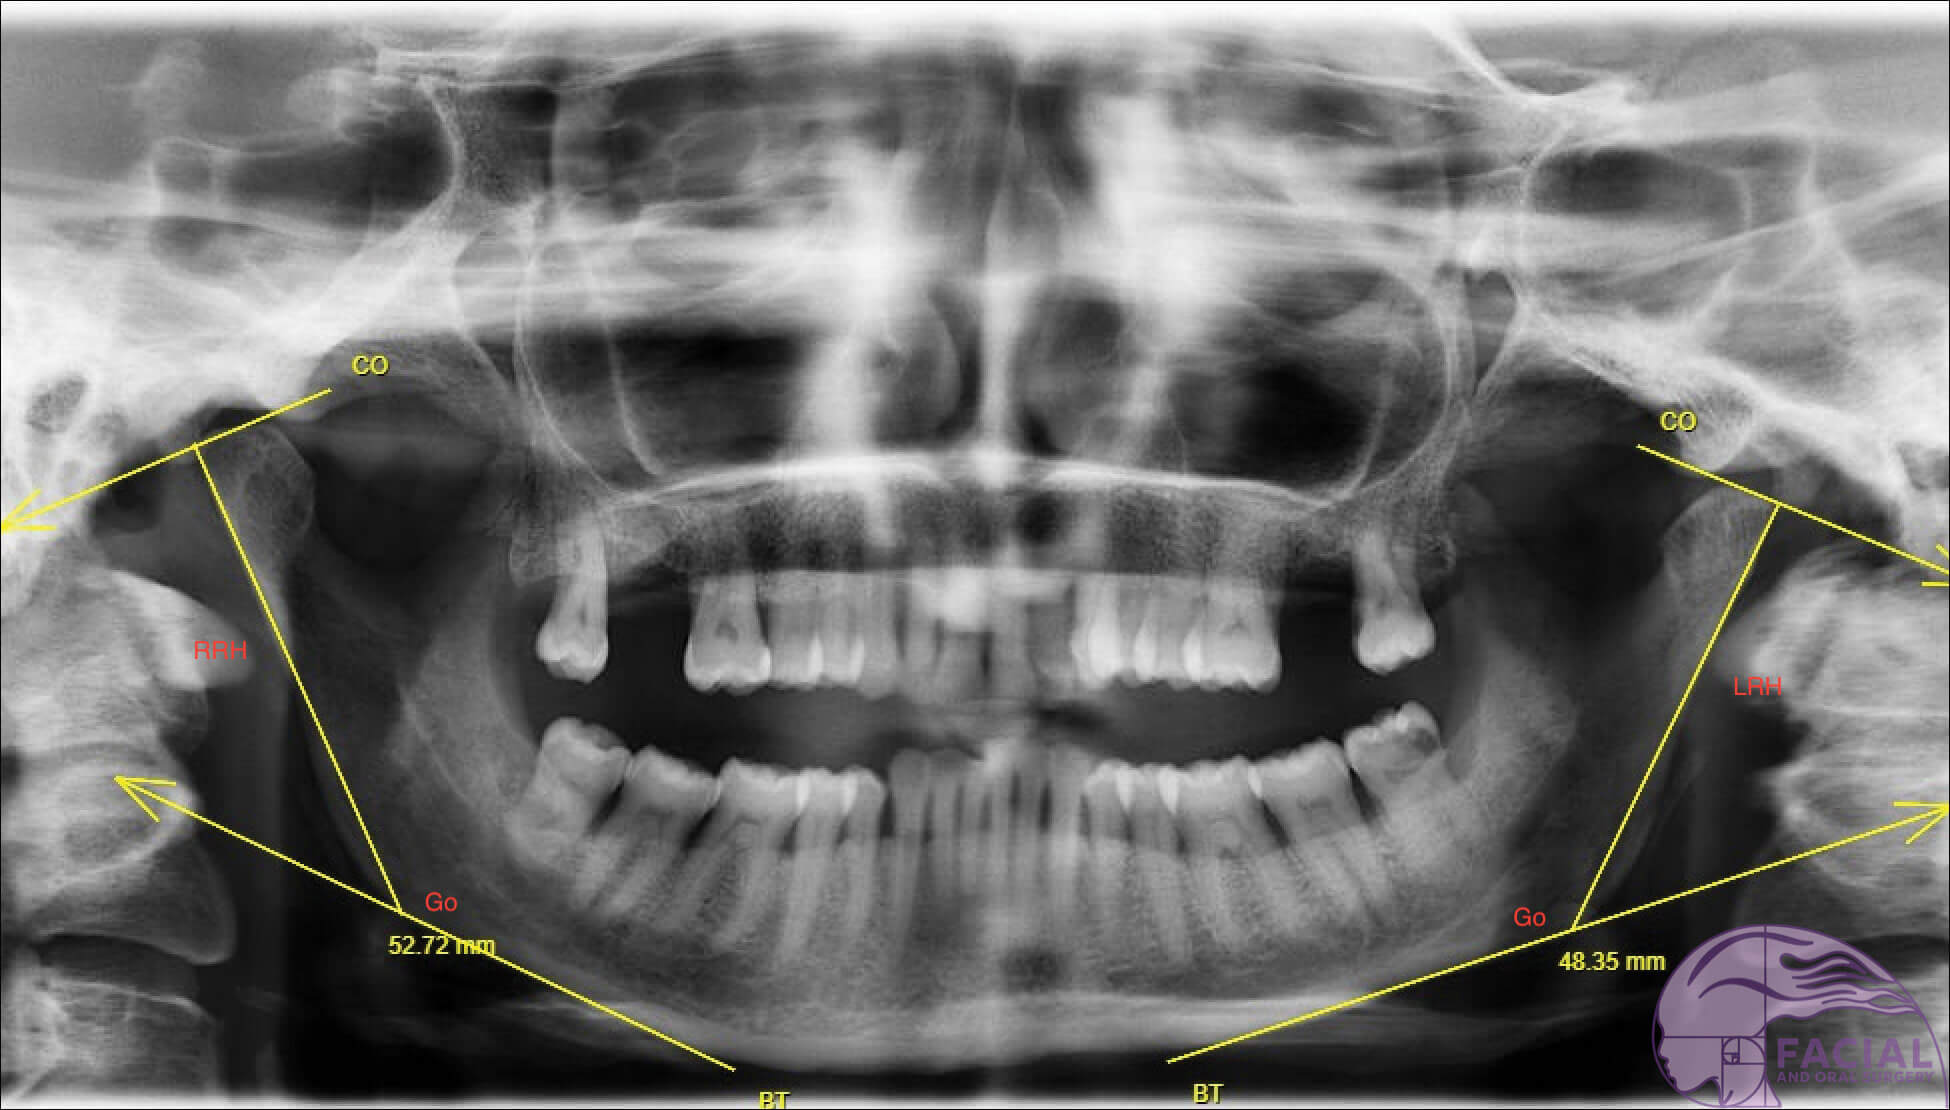

In 1988, Habets, et al. [14] introduced the asymmetry index using orthopantomograms to analyse vertical asymmetries in the mandible, in cases of ramus and / or condylar height asymmetries, which contribute to horizontal / sagittal asymmetries observed. Index values over 6% vertical difference between the right and left sides were considered to have vertical asymmetry, as values less than this are likely due to technical measuring errors.

Figure 2a: Case 1 Orthopantomagram: Yaw dominant mandibular asymmetry with chin midline deviation to right.

Figure 2b: Case 2 Orthopantomagram: Roll dominant mandibular asymmetry with no chin midline deviation.

Right ramus height (RRH). Left ramus height (LRH).

Positive asymmetry index (AI) values indicate that the right mandibular ramus is longer; a negative AI indicate an elongated left side. The AI [14] to evaluate the severity of asymmetry between heights of both sides of the ramus of the mandible:

AI, % = RRH - LRH / RRH + LRH × 100%

- Diagnosis: Skeletal base III growth discrepancy, due to maxillary hypoplasia complicated by left hemi-mandibular elongation causing mandibular asymmetry to the right. Yaw dominant mandibular asymmetry (see Figure 1, 2a and 3).

- Diagnosis: Parry-Romberg Syndrome (i.e. Left hemifacial atrophy) affecting left side of mandible and soft tissues including muscle and fat. The left ramus height is 5mm shorter compared to the normal right side but no disocclusion due to dental compensation by over-eruption of teeth on left side. Roll-dominant asymmetry (see Figure 2b).